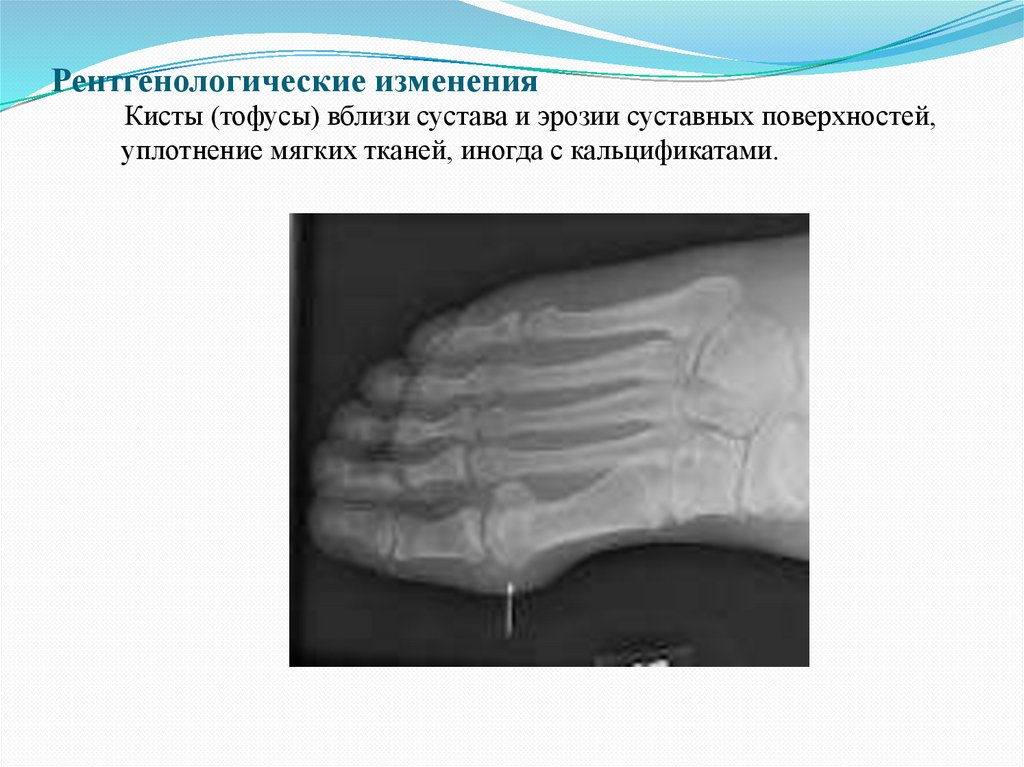

составила 82,6%.

Рентгенологические изменения